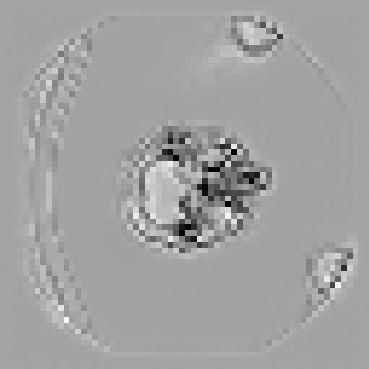

The hypothesis of this experiment is that if the synthetic images generated by our model resemble real medical images in distribution, a segmentation network trained on real data should yield similar performance on synthetic data. By comparing the segmentation results across real and synthetic images, we can quantitatively assess the structural fidelity and semantic consistency of the generated data. The results confirm that segmentation performance on synthetic images is highly comparable to that on real images, indicating that our model successfully captures anatomically relevant structures. This suggests that synthetic data are not only realistic but also potentially beneficial as an augmentation strategy to improve segmentation tasks. Visualizations of the segmentation output are presented in Figure 6.

The goal of our research is not to generate fancy or visually appealing images, but rather to produce images that are useful for downstream tasks. Our focus is on creating synthetic data that have small domain gap with real data, helping to address the bottleneck of data scarcity in the field of machine learning for medical imaging. By generating images that are meaningful for specific tasks, we aim to improve the performance of models in clinical applications, ultimately driving advancements in medical image analysis where labeled data are often limited. In this experiment, We first train a 3D segmentation network using the images and the corresponding semantic maps from training set of the real Duke Breast dataset. The model and training details can be found in the Appendix B. The purpose is to allow the network to learn how to segment anatomical structures from real MRT data. After completing the training phase, we evaluated the segmentation network on four different datasets as shown in Table 2: (1) real images from the Duke Breast dataset training set, (2) real images from the Duke Breast dataset test set, (3) synthetic images generated by our SegGuidedDiff model [26] using semantic maps from the Duke Breast test set, and (4) synthetic images produced by our Med-LSDM model based on the same semantic maps. By evaluating the segmentation results on different real and synthetic images, we aim to investigate the effectiveness of the generative model in producing realistic images that could yield similar segmentation results to real data, suggesting that real and synthetic images lie in similar regions of the data distribution.